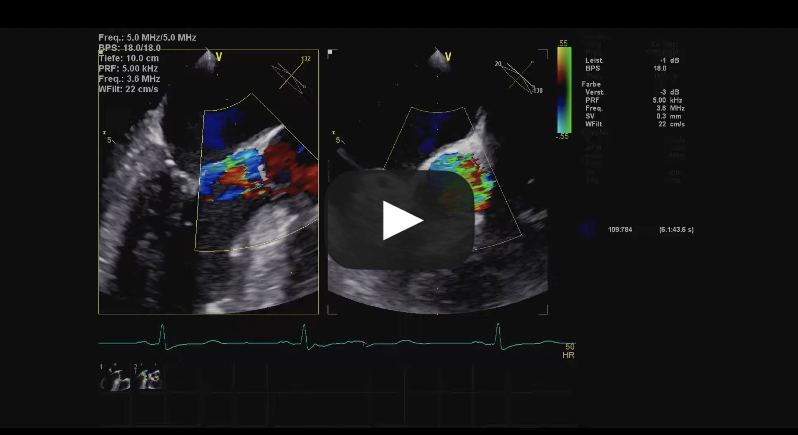

Bicuspid Aortic Valve Repair

Source: Cardiac Research & Education Saar GmbH, used with permission.